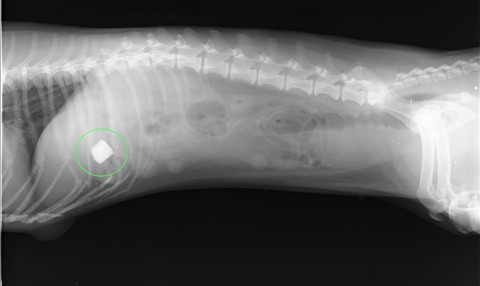

X線検査を行った所、お腹の中に白い四角い物体(緑丸の中)が確認されました。

X線検査では、金属などの硬い物質が白く写ります。